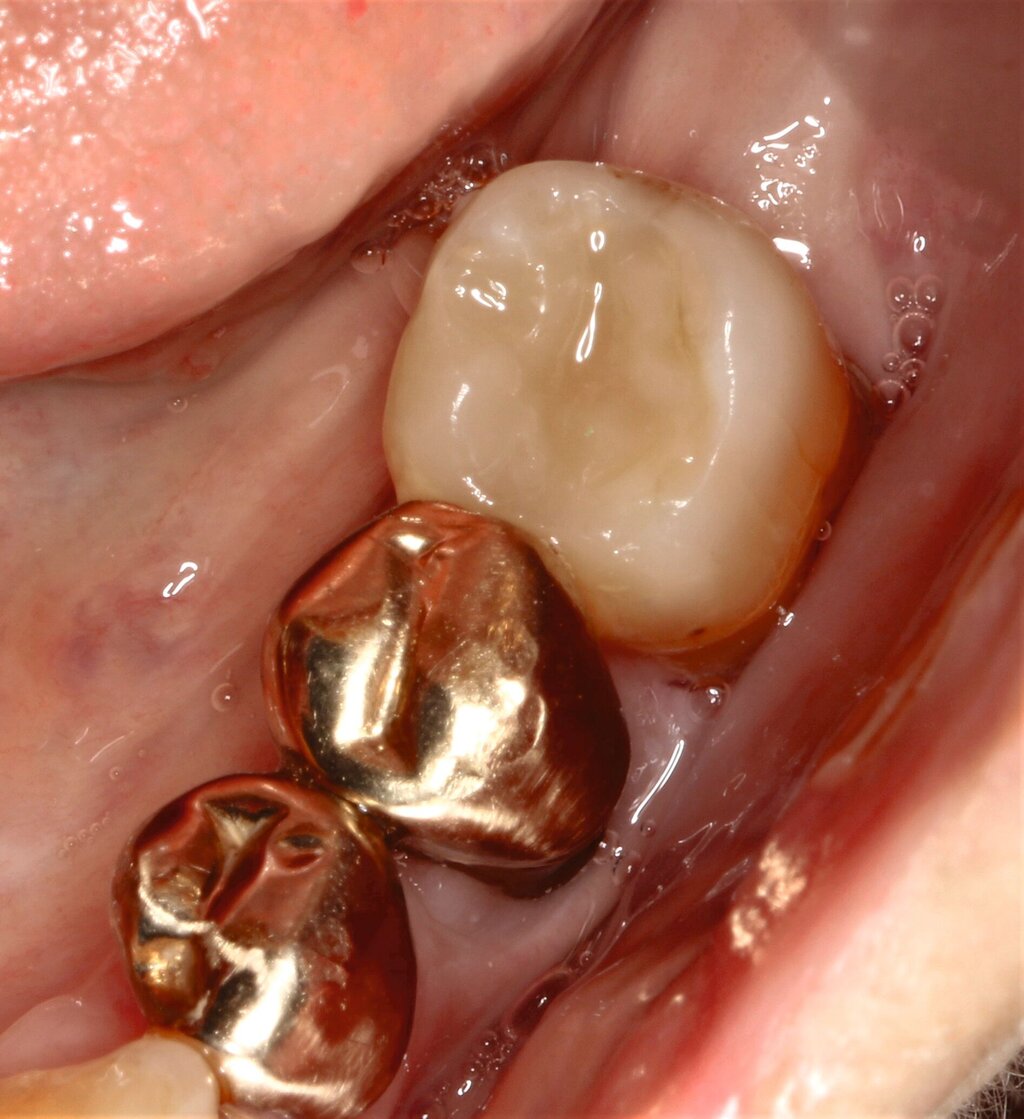

Die hochbetagte Patientin war bereits viele Jahre in der Poliklinik für Zahnerhaltung des Universitätsklinikums Tübingen zahnmedizinisch betreut worden, allerdings aus Sorge vor einer Corona-Infektion von Ende 2019 bis August 2023 knapp vier Jahre der zahnärztlichen Versorgung ferngeblieben. Grund der Wiedervorstellung war dann ein wenige Tage zuvor stattgefundener Füllungsverlust am Zahn 36. Hier bemerkte die Patientin eine an der Zunge störende scharfkantige Fraktur des Molaren (Abbildungen 2 und 3). Weitere Schmerzen oder Beschwerden gab sie nicht an. Im Rahmen der zahnärztlichen Untersuchung konnten multiple Rezessionen und diverse arretierte Brown-Spot-Läsionen festgestellt werden.

Die von ihr als störend empfundene scharfkantige Füllungsfraktur konnte noch am selben Tag mit einer direkten Kompositrestauration (Reparaturrestauration unter Verwendung des Cojet-Systems, 3M Espe; Monobond Plus, Ivoclar; Optibond FL Adhäsiv, Kerr; Ceram X Spectra STHV, Dentsply Sirona) versorgt werden. Nach der weiteren Befunderhebung und der Empfehlung zur Wiederaufnahme der UPT wurde die Patientin über eine parodontale Schienungsmöglichkeit der Unterkieferfrontzähne aufgeklärt, die ihr an einem Folgetermin samt UPT wenige Wochen später angeboten wurde.